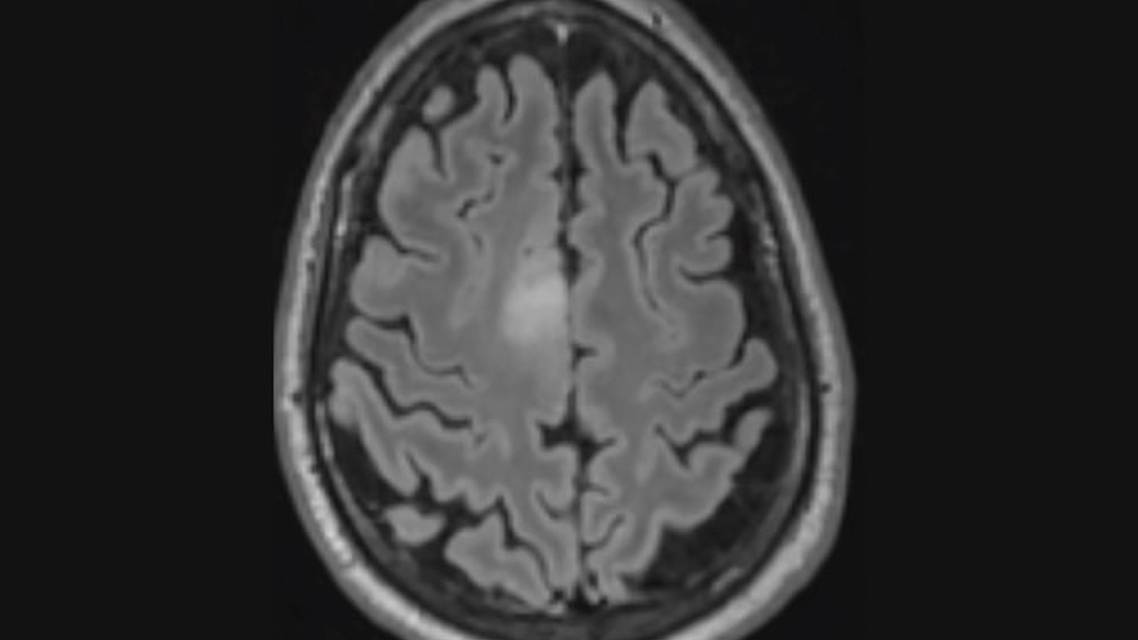

On neurologic examination, Mr L had diminished sensation to temperature in his right leg. Otherwise, sensation to light touch, temperature, and proprioception was intact in all extremities. The rest of the neurologic and cognitive examination was unremarkable. Brain MRI revealed a 1.4 x 1.5 cm right superior frontal gyrus lesion. The lesion was hyperintense on fluid-attenuated inversion recovery (FLAIR) imaging (Figure 1) and was not associated with any enhancement (Figure 2).

D, The radiographic appearance of a cortical-subcortical non-enhancing expansile fluid-attenuated inversion recovery (FLAIR) hyperintense lesion and the histologic description of “perinuclear halos” are most consistent with an oligodendroglioma.